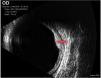

Choroidal hemangioma (CH) is a benign vascular tumor dependent on the choroid. Two types of lesions are distinguished: circumscribed (CCH), the most frequent variant, and diffuse (DCH), normally associated with Sturge-Weber syndrome.

HCC appears as an orange mass that can present asymptomatically, however, when it produces symptoms, the most frequent is decreased visual acuity due to neurosensory retinal detachment. Due to its benign nature, only those that produce symptoms should be eligible for treatment. Knowledge of this pathology and its correct differential diagnosis is very relevant to establish the appropriate diagnosis and treatment, avoiding unnecessary treatments. There is currently a wide variety of multimodal diagnostic imaging tests that allow us to identify and adequately monitor this tumor. In addition, in recent years, there has been a change in the paradigm of the treatment of these tumors thanks to the use of photodinamic therapy, which has led to a significant improvement in the visual prognosis of these patients. This has been due to the use of photodynamic therapy as the treatment of choice for HCC.